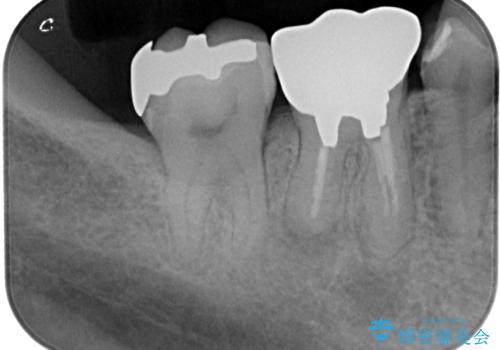

- 適合の良くない銀の詰め物が入っており、白い詰め物へのやり替えをご希望された患者様です。

メタルインレーを除去したところ、虫歯ができていたため取り除いたうえでハイブリッドインレー修復を行いました。

インレーセット時には唾液の侵入を防ぐためにラバーダム防湿を行っています。

Ⅲ級咬合の患者さまで、奥歯への負荷が強いため、セラミックよりも破損のリスクが低いハイブリッドインレー治療を行いました。